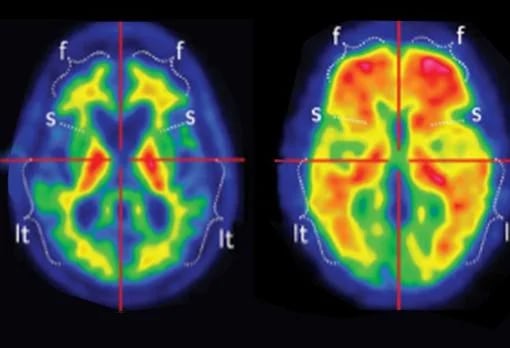

Para llevar a cabo el estudio, los investigadores evaluaron a 76 voluntarios mediante electroencefalogramas (EEG) mientras participaban en un juego de aprendizaje basado en recompensas. Durante la prueba se utilizaron alimentos como: 1) dulces, 2) chocolate, 3) papas fritas y 4) pochoclo.

No obstante, los registros eléctricos mostraron que las áreas cerebrales vinculadas con la recompensa mantenían una respuesta similar ante las imágenes del alimento, incluso después de que los participantes estuvieran completamente saciados.

“Lo que vimos es que el cerebro simplemente se niega a restarle importancia a lo gratificante que parece una comida, sin importar lo lleno que estés. Incluso cuando las personas saben que no quieren la comida, incluso cuando su comportamiento muestra que han dejado de valorarla, sus cerebros continúan enviando señales de recompensa en el momento en que aparece la comida”, señala Sambrook.